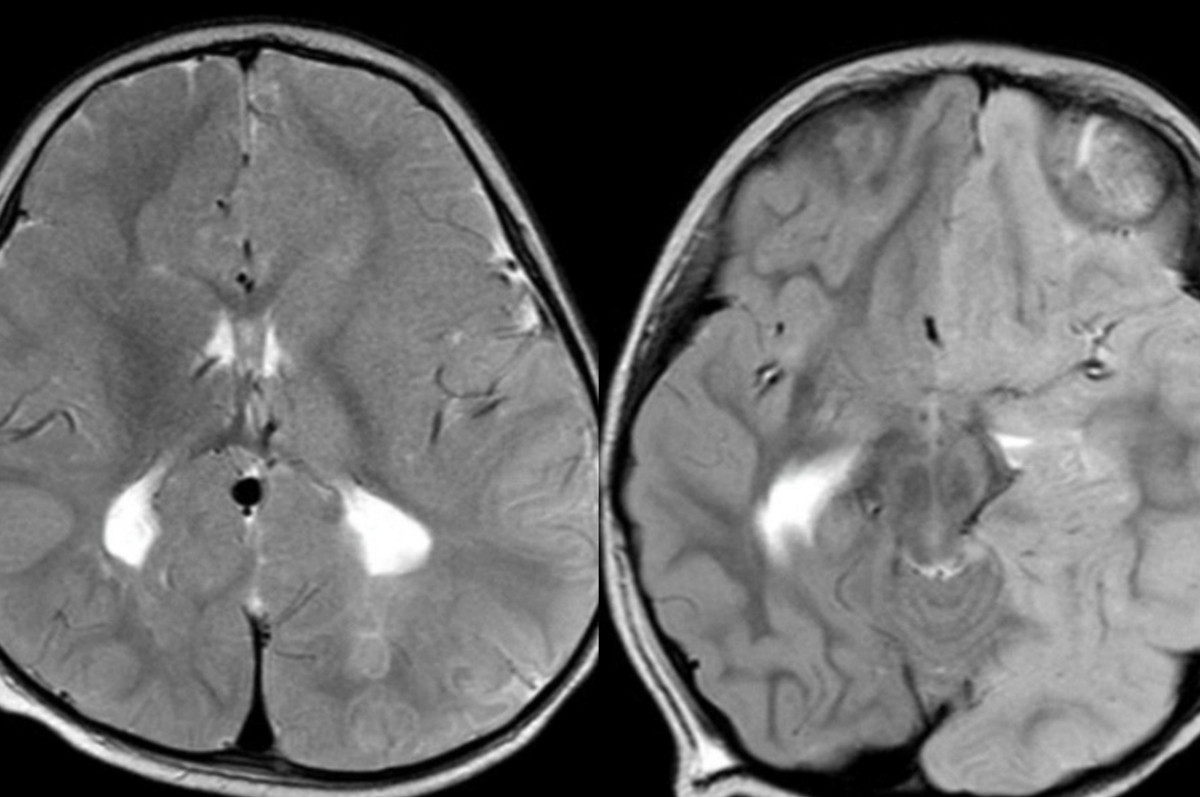

Bệnh nhi N. được đặt nội khí quản, chuyển khoa Hồi sức tích cực Nhiễm. Kết quả MRI sọ não cho thấy bé có tổn thương hạn chế khuếch tán lan tỏa ở bán cầu não trái trong khi vỏ não phải bình thường.

BS.CKII Đỗ Châu Việt, Trưởng Khoa Hồi sức tích cực Nhiễm Bệnh viện Nhi Đồng 2 cho biết, kết quả MRI sọ não của bé X. cũng cho thấy có tổn thương kèm phù não gần như toàn bộ nửa bán cầu trái, đẩy lệch đường giữa sang phải, bán cầu não phải bị ép xẹp.